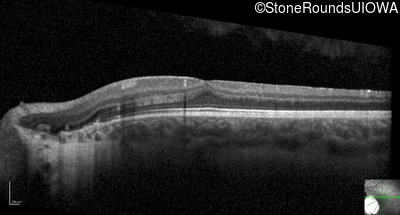

Optical Coherence Tomography - Right - 20/40 +2

Exemplar / OCT Stack